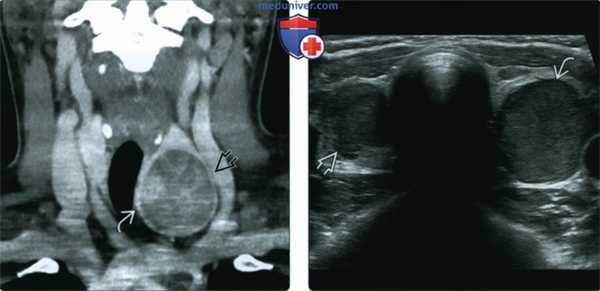

(Слева) КТ с КУ, коронарная проекция, фолликулярная аденома щитовидной железы, которая выглядит как новообразование низкой плотности, расположенное в толще щитовидной железы и неравномерно накапливающее контрастное вещество. Обратите внимание на четкие контуры аденомы, а также на то, что она сдавливает трахею, но не прорастает в нее.

(Справа) УЗИ в поперечной плоскости, на котором определяются узлы обеих долей щитовидной железы. Узел слева имеет четкую капсулу, при гистологическом исследовании операционного материала была выявлена фолликулярная аденома. Правый узел имеет несколько нечеткий латеральный край; в дальнейшем новообразование оказалось фолликулярной карциномой щитовидной железы.